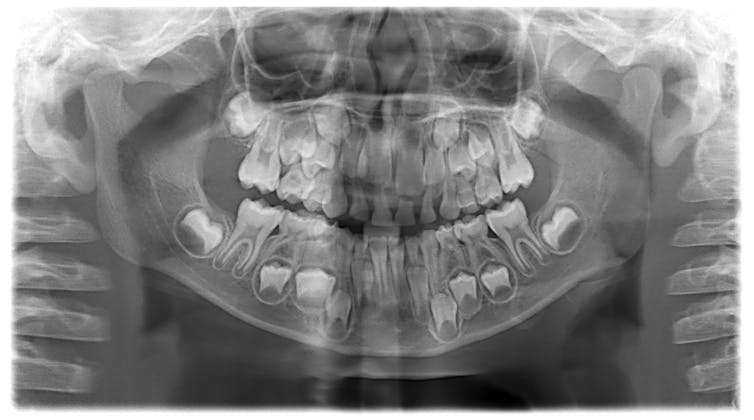

La plupart des gens finiront par avoir 20 dents de lait. Ce sont nos premières dents. Elles seront remplacées par des dents adultes lorsque nous grandirons. La dernière dent de lait tombe habituellement vers l’âge de 12 ans.

Souvent, nous ne le remarquons pas, mais en même temps que nos premières dents de lait commencent à tomber, nous avons aussi de nouvelles dents à l’arrière de notre bouche qui poussent. Ce sont nos premières molaires adultes.

Vers notre sixième anniversaire, on peut commencer à voir et à sentir des changements dans notre bouche. Nos dents de lait sont usées par les morsures et les morsures qu’elles ont faites. Nous avons aussi grandi, tout comme nos mâchoires et nos bouches. Il est donc temps d’avoir de plus grosses dents !

Les racines des dents sont généralement longues et lisses. Les dents de devant n’ont généralement qu’une racine, mais les dents de derrière peuvent avoir jusqu’à trois racines. Lorsque le moment est venu, notre corps possède des cellules spéciales qui rongent lentement les racines des dents. Au fur et à mesure que les racines raccourcissent, les dents commencent à se détacher. Finalement, la racine disparaît et la dent tombe !

Peu de temps après, une nouvelle dent adulte commencera à pousser dans l’espace laissé par la dent de lait.

Les dents d’adulte peuvent sembler un peu bizarres au début — elles sont habituellement un peu plus jaunes, peuvent avoir des bosses et des sillons et sont bien sûr beaucoup plus grosses. Elles ont aussi des racines beaucoup plus longues. Les dents adultes sont fabriquées de cette façon afin qu’elles soient assez fortes pour durer toute notre vie. Vous mastiquerez de la nourriture pendant de nombreuses décennies.